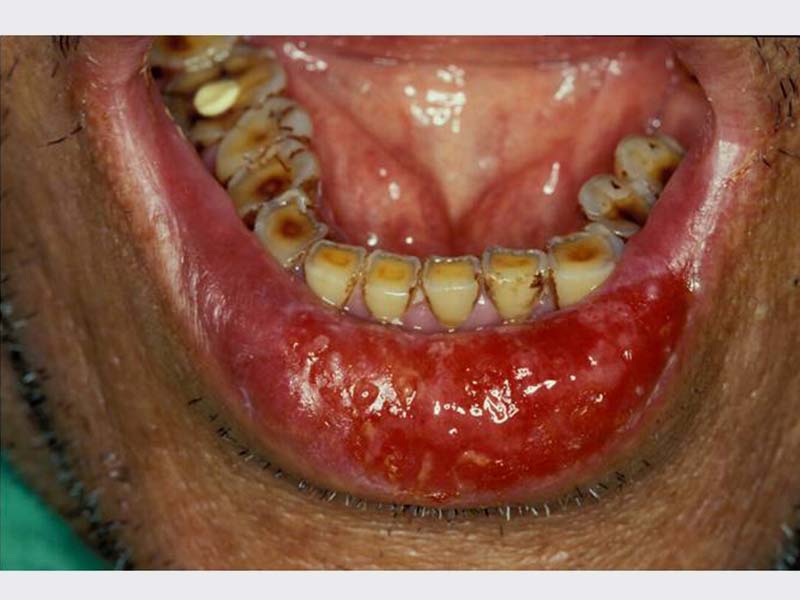

口腔黏膜病變治療

• 口腔黏膜病變治療